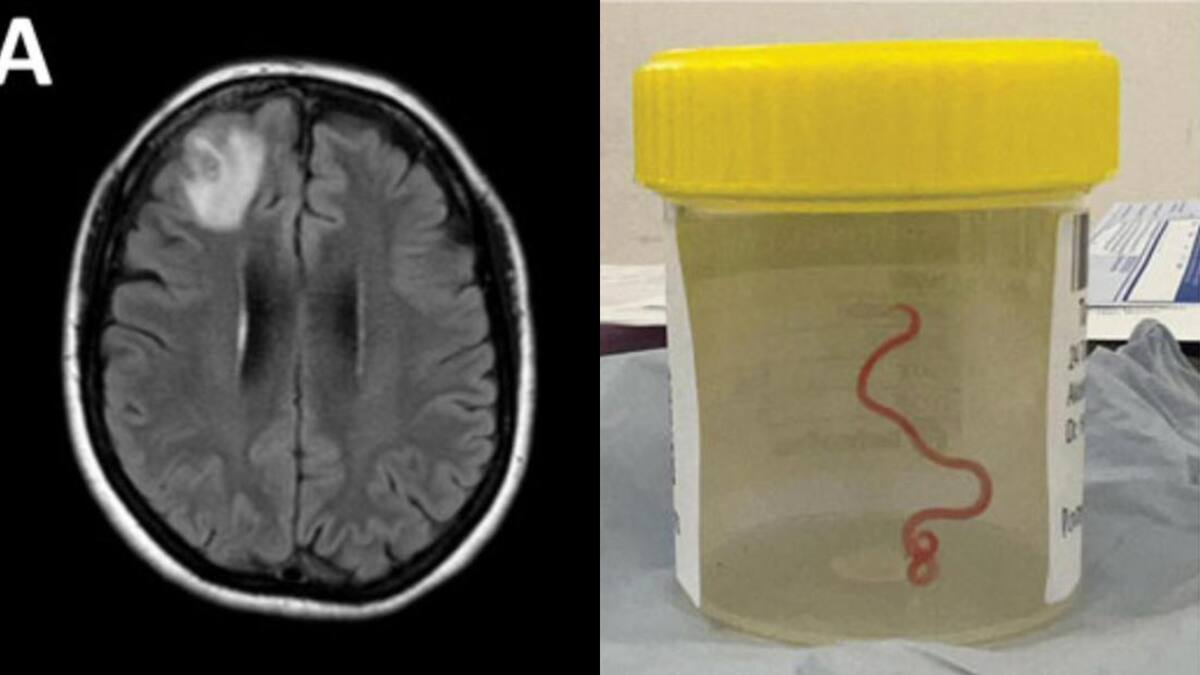

En 2022, la paciente se sometió a una resonancia magnética tras experimentar trastornos en la memoria y depresión. Las imágenes del cerebro de la paciente revelaron que la mujer tenía una lesión atípica en el lóbulo frontal derecho.

Un neurocirujano del Hospital de Canberra exploró la anomalía y fue entonces cuando se encontró la inesperada lombriz intestinal de ocho centímetros.

El parásito fue extraído, vivo y retorciéndose, de la paciente durante de una cirugía cerebral, de la que no se precisa la fecha, y actualmente la mujer continúa siendo examinada por el equipo de especialistas en enfermedades infecciosas y cerebro.